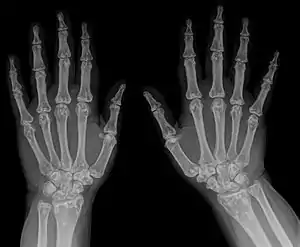

| Diagnostic method | X-ray, ultrasound[3] |

- Osteopoikilosis

- Metaphysis abnormality

- X-ray